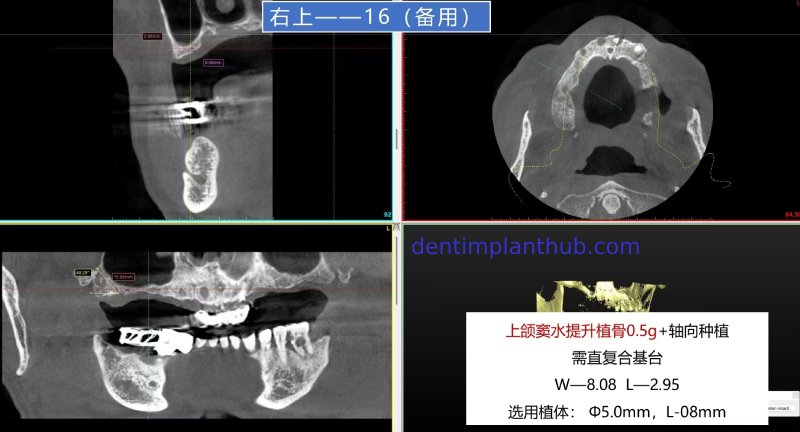

The specific conditions of each tooth position and the implant plan

For tooth 16 as an alternative plan, it has a width of 8.08 and a height of 2.95. An implant with a diameter of 5 and a length of 8 is selected. It will be implanted axially. A maxillary sinus floor elevation is required, with 0.5 grams of bone grafting material to be implanted, and a straight composite abutment is needed.